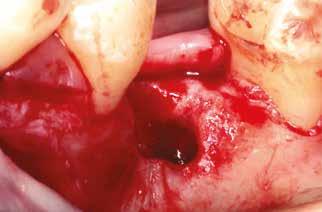

A socket-shield technika lényege az azonnali implantációt megelőző részleges fogeltávolítás. Dekoronálást követően a megmaradt gyökér több darabban kerül eltávolításra, azonban a

falat mint „pajzsot”, meg kell őrizni, ezzel megelőzhető a bukkális csontfal egyébként fiziológiás reszorpciója (4. és 5. kép). A sebészi technika különös körültekintést követel meg, nehogy a bukkális „gyökérpajzs” megmozduljon, ezzel a bukkális oldalon megmaradt periodontális ligamentumok sérülését kockáztatnánk, amely az esetenként

igen vékony (0,5-1,5 mm), bukkális köteges csont (bundle bone) lebomlásához vezetne a periodontális ligamentumok felől megszűnő vérellátás miatt.

A teljes palatinális gyökérrészlet és az apex eltávolítása után a megmaradt bukkális dentinfalat kb. 0,75-1 mm-re elvékonyítva, továbbá a koronális dentinszélt csontszintig preparálva készül el a megmaradó foggyökér-részlet. Az összes endodontális maradvány (pulpa, illetve esetleges gyökértömés), valamint az apex teljes mértékű eltávolítása kulcsfontosságú az implantátum sikeres osszeointegrációja szempontjából.